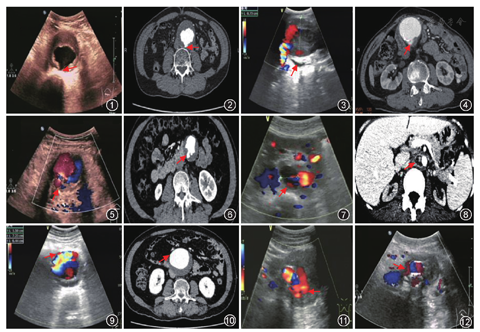

患者因体检发现AAA 4例,腹部、腰背部疼痛者17例,摸到腹部搏动性包块者14例。腹痛患者中,伴有明显腹部、腰背部疼痛者14例,腰部不规律隐痛者3例。CDU显示3例瘤壁不连续(图1,图2)。4例新月征(图3,图4)。3例裂隙征(图5,图6)。2例瘤体局部突出,呈囊袋状(图7,图8)。余23例瘤壁局部菲薄(图9,图10)。CTA提示瘤壁不连续、新月征、裂隙征及囊袋状凸起例数与CDU相同,余21例患者瘤壁局部菲薄,2例未发现瘤壁菲薄征象。CDU误诊率为5.7%(2/35)。所有患者无主动脉披挂征,未见夹层,瘤体旁及后腹膜无血肿形成,无腹腔游离液。